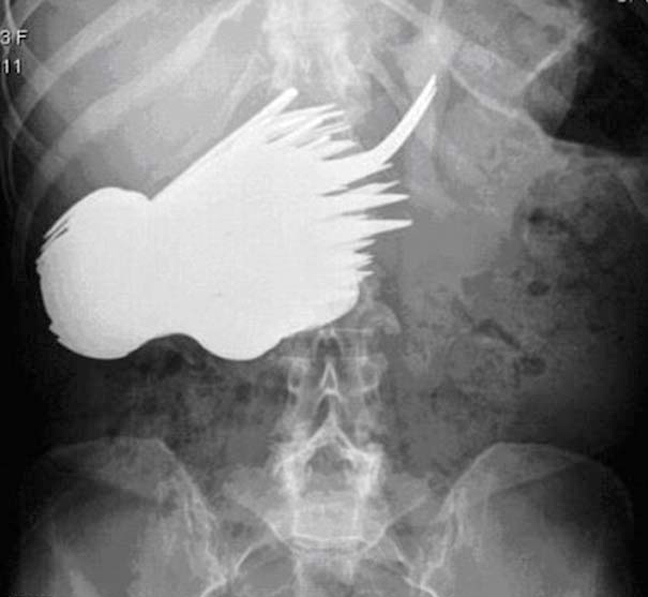

Δαχτυλίδι αρραβώνων Κλειδί Κουζινικά Χελι Μαγνητάκια Καρφιά 78 Κουτάλια και πιρούνια Φίδι

Ο,ΤΙ ΝΑ 'ΝΑΙ #φωτογραφίες Όταν μιλούν οι ακτινογραφίες! Αντικείμενα -και όχι μόνο- μέσα σε ανθρώπινα σώματα… 24·09·2013 13:33 16 σχόλια Δαχτυλίδι αρραβώνων Κλειδί Κουζινικά Χελι Μαγνητάκια Καρφιά 78 Κουτάλια και πιρούνια Φίδι